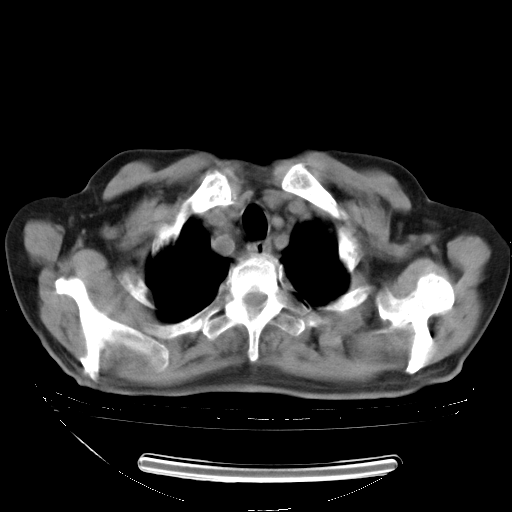

今天复查肺部CT,发现双肺广泛磨玻璃样改变。所以我把3月19日和5月9日相隔50天的肺部CT上传。请大家会诊。

5月9日肺部CT(在4月27日齐鲁医院肺部CT描述部分肺组织磨玻璃样改变,12天后肺组织广泛磨玻璃样改变)

2009年5月9日肺部CT

大致读了系列胸部CT:纵隔窗无明显异常,肺窗:从4、27至今:主要是双肺中下野外带可见毛玻璃样改变,目前处于急性肺泡炎阶段,至于原因考虑1、结替组织或胶原血管性疾病所致?2、恶性疾病如恶组在肺部所致的表现或细支气管肺泡癌?3、药物或其它原因如肺蛋白沉着症所致肺泡炎目前不太可能?总之,明天就去请我院的呼吸科、感染科、血液科和临免专家会诊哈。